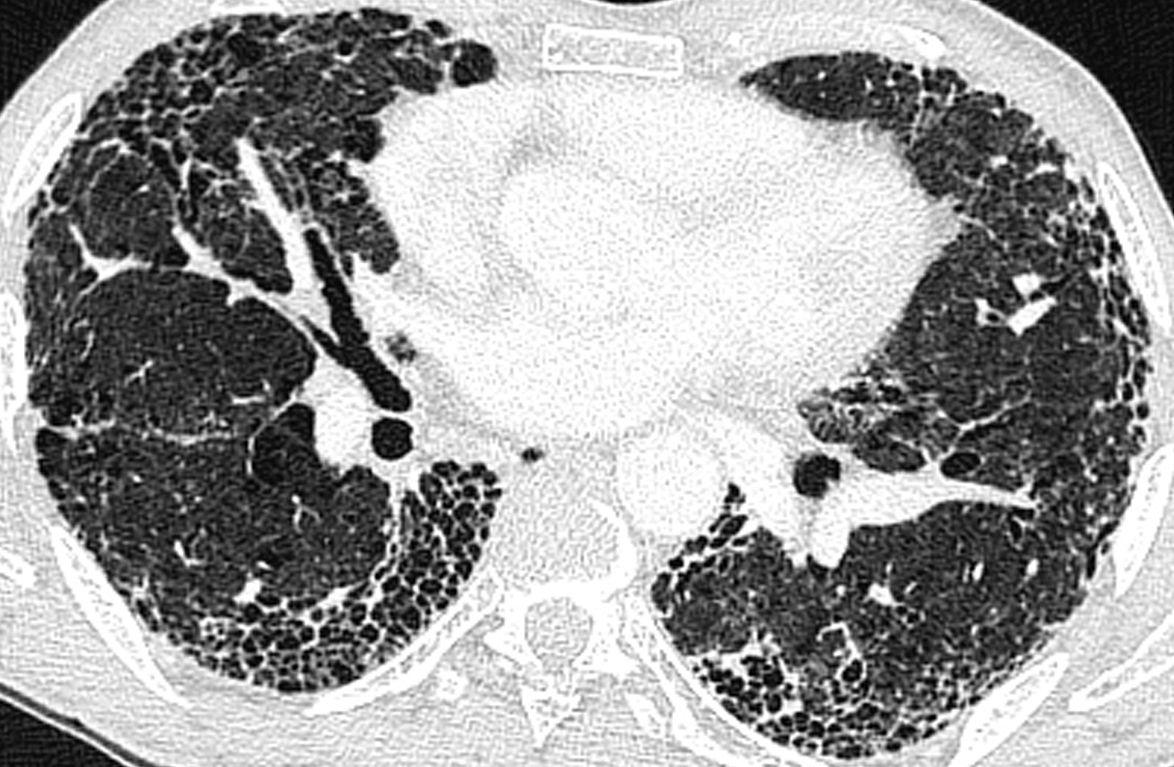

Un scanner thoracique a été réalisé.

Figure 5.

Question 7 - Quelle(s) anomalie(s) constatez-vous (une ou plusieurs réponses exactes) ?

Il s’agit ici d’un tableau de pneumopathie interstitielle diffuse avec un pattern de fibrose. La sémiologie des lésions élémentaires du syndrome interstitiel déjà décrit à la question 2 est associée à des signes de fibrose qui peuvent comprendre de manière générale deux grandes entités :

1) de la destruction parenchymateuse : typiquement les microkystes (rayon de miel) qui sont de petits « trous », avec paroi, à prédominance sous-pleurale ;

2) des distorsions architecturales dont la plus connue et fréquente est la bronchectasie de traction (différent de la dilatation des bronches qui est une maladie inflammatoire des bronches, la bronchectasie de traction correspond juste à une distorsion de la bronche par traction interstitielle).

Concernant l’origine de la PID, l’on s’orientera ici préférentiellement vers l’asbestose, car le scanner montre des images qui sont plutôt en faveur de pneumopathie interstitielle commune (PIC) (absence de verre dépoli), et l’alvéolite est neutrophilique. Dans le cadre d’une PID médicamenteuse, l’alvéolite est plutôt lymphocytaire, voire éosinophilique, et les images sont plutôt en faveur d’une pneumopathie interstitielle non spécifique (PINS) (verre dépoli +++). Enfin, si l’alvéolite est plutôt neutrophilique ou lymphocytaire dans la PID de la dermatopolymyosite, le scanner montre le plus souvent des images de pneumopathie interstitielle non spécifique (PINS).

La PIC et la PINS sont des tableaux radiologiques décrits ci-dessous.